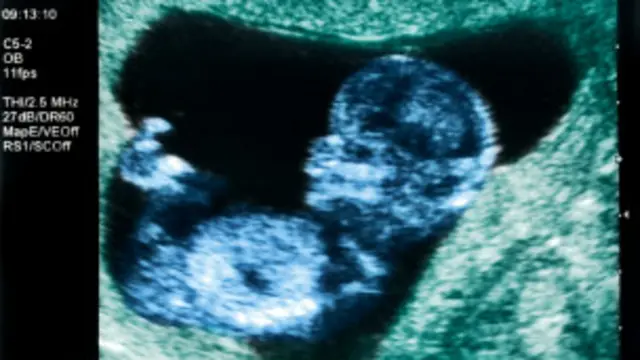

پزشکان هم اکنون اعلام کردهاند که در پی انتقال جنین به رحم این زن، که از راه آی وی اف (IVF) یا لقاح مصنوعی تشکیل شده بود ، او نزدیک به دو هفته باردار است.

به گفته پزشکان در صورتی که دوران حاملگی دریا سرت با سلامت ادامه یابد و نوزادی متولد شود، این اولین بار در تاریخ علم پزشکی خواهد بود که نوزادی از یک رحم پیوندی متولد میشود.